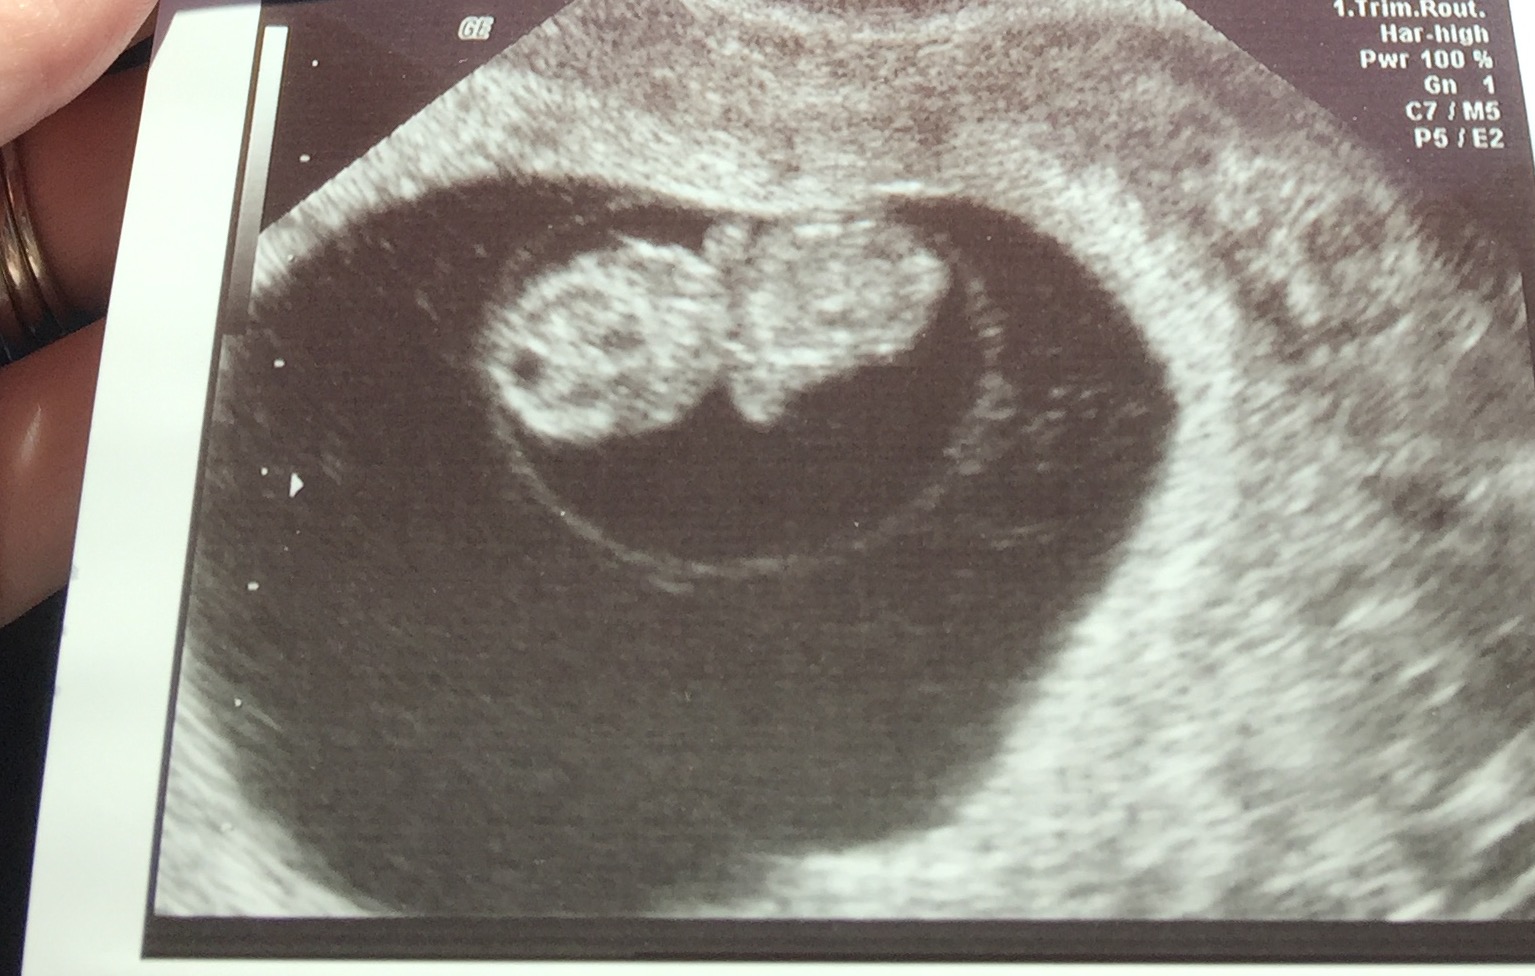

8 week ultrasound and there's twins! We were only able to see one heart beat and they thought I'm a week behind where I thought I was so please send good growing thoughts my way. Headed back in a week to hear Baby B. also if anyone has had experience in this area, please advise.

8 week ultrasound and there's twins! We were only able to see one heart beat and they thought I'm a week behind where I thought I was so please send good growing thoughts my way. Headed back in a week to hear Baby B. also if anyone has had experience in this area, please advise.</p>